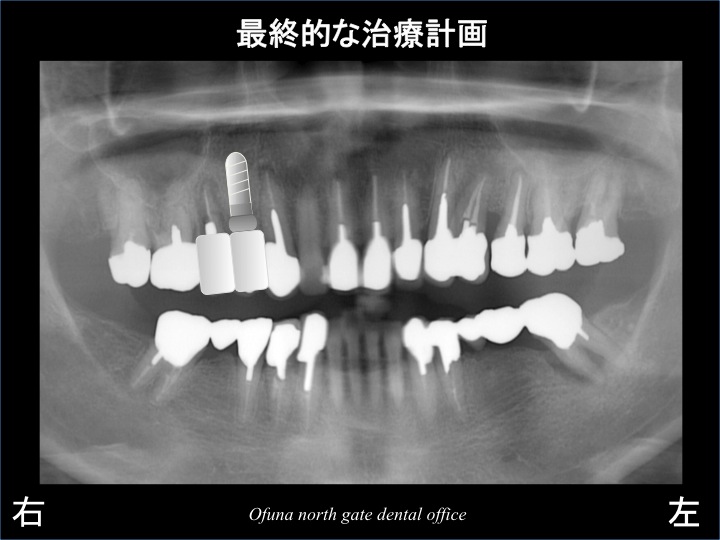

しかし、噛み合わせ等を十分に検討した結果

以下のような最終的な治療計画は以下のようになりました。

上記のような治療計画により、

歯根破折 を起こした部位には、埋入を避けることにより、GBR法(骨増大法) を行わない!

治療費を最小限にするために 埋入するインプラントは、1本のみにする!

ということが可能になります。

1本のインプラントで2歯分を作成する方法をカンチレバー と言います。

噛み合わせが安定している場合には可能な治療方法です。